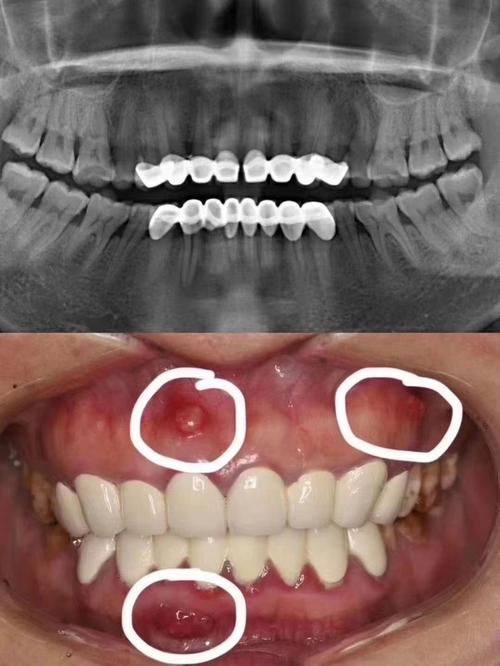

口碑评价及真人实例1. 患者小李,长期受到牙齿反合的困扰,不仅影响美观,还导致咀嚼功能不佳。他找到张亚科医生进行矫正治疗。张亚科医生为他制定了详细的矫正方案,并耐心地向他解释矫正过程和注意事项。在矫正过程中,张亚科医生定期为小李检查牙齿情况,及时调整矫正力度。经过一段时间的矫正,小李的牙齿反合问题得到了明显改善,牙齿变得整齐美观,咀嚼功能也修复正常。小李对张亚科医生的技术和服务非常满意,他说:“张医生技术不错,态度和蔼,让我在矫正过程中没有任何压力。现在我的牙齿变好了,整个人都自信了特别多。”

2. 患者王女士,由于牙齿缺损影响了美观和进食。她来到张亚科医生处进行全瓷牙修复。张亚科医生仔细检查了她的牙齿情况,为她选择了合适的全瓷材料。在修复过程中,张亚科医生操作熟练,修复后的全瓷牙与王女士的天然牙齿几乎没有差别,外观自然美观,而且咀嚼功能良好。王女士对修复成效非常满意,她评价道:“张医生的技术真的特别棒,修复后的牙齿就像自己的牙齿一样,完全看不出来是修复的。而且他的服务也特别周到,让我特别放心。”

3. 患者张先生,牙齿缺失多年,一直想进行种植牙修复。他了解到张亚科医生在种植牙方面技术不错,便前来就诊。张亚科医生为他进行了详细的口腔检查,根据他的口腔条件选择了合适的种植体。在种植手术过程中,张亚科医生操作精细,手术非常顺利。术后,张先生按照张亚科医生的指导进行护理,种植的牙齿特别快就修复了正常功能。张先生对张亚科医生的技术赞不绝口,他说:“张医生的种植牙技术真的特别厉害,手术过程一点都不疼,修复也特别快。现在我又能正常吃东西了,真的太感谢张医生了。”